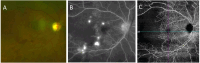

Results: The following clinical manifestations were found: keratoconjunctivitis sicca (n = three patients), anterior uveitis associated with an inflammatory pseudo-tumor orbital mass (n = one patient, one eye), episcleritis and periorbital edema (n = one patient, two eyes), posterior scleritis (n = one patient, two eyes), bilateral papillary edema in the context of idiopathic intracranial hypertension (n = one patient, one eye), inflammatory optic neuritis (n = one patient, one eye), and lupus retinopathies with varying degrees of capillary occlusions mainly arteriolar (n = seven patients, 13 eyes) and larger arteries or veins (retinal arteries occlusions and retinal veins occlusions) (n = one patient, two eyes). Some patients presented with combined ophthalmological manifestations.Systemic SLE was discovered by its ophthalmic manifestation in three cases (23%) and was previously known in the other 10 cases (77%). On average, ocular symptoms were seen 8 years after the initial diagnosis of SLE. Other systemic SLE disorders included cutaneous disorders (77%), joint disorders (38%), central nervous system (CNS) disorders (23%), renal disorders (38%), and oral ulcers (23%).Treatment of the ophthalmic system manifestations of lupus included local steroid therapies along with systemic immunosuppression.The most common laboratory ACR criteria were: high levels of antinuclear antibodies (ANA) (100%), positive anti-Sm (64%), anti-dsDNA (27%), low complement levels (27%), and positive antiphospholipid (APL) antibodies (18%).

Discussion: SLE activity in the ophthalmic system is characterized by its functional severity and the range of involvement can be categorized by anatomical involvement: presence of anterior uveitis, episcleritis, scleritis, periorbital edema, posterior uveitis with retinal vascular ischemia, or papillary edema. Not currently part of the diagnosis criteria of the SLE ACR given its rarity, the ocular localization of the pathology led to the diagnosis of SLE in three cases; thus, developing a greater understanding of ocular lupus may help in identifying and treating systemic manifestations of lupus earlier.